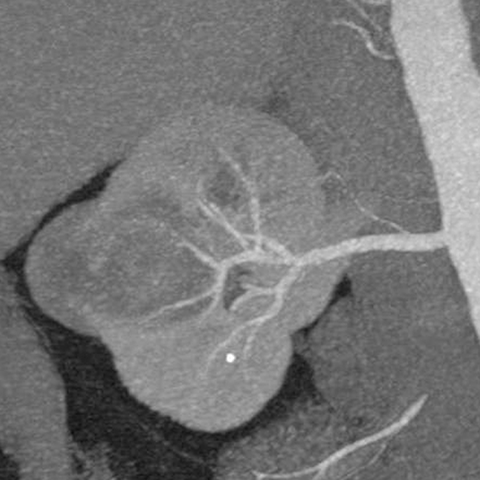

67-year-old male with flank mass and hematuria [3 of 3]